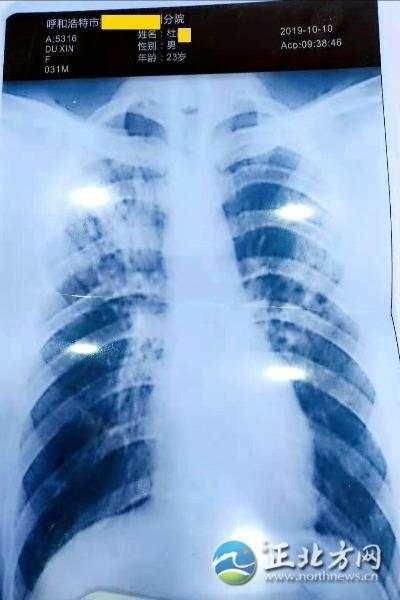

杜某找人伪造的胸片显示他得了严重的肺结核

由于肺结核具有很强的传染性,事件引发了班上18名与他近距离接触的5岁左右幼童家长的恐慌。10月10日至10月31日间,由校方支付费用,班里的家长们紧急带着各自的孩子奔赴各大医院进行结核菌素化验,18名儿童中竟有2名儿童的结核菌试验报告单呈阳性,家长们纷纷站出来表示要维权。眼看事态扩大,校方经过走访也已经发现杜某伪造病历的细节,杜某不得已,站出来向家长们澄清:“我没病。”

当日下午,为了验证杜某的说法,由家长指定医院和医生,大家带着杜某去拍了胸片,并做了痰化验。诊断意见为,胸部平片未见异常。胸片也与杜某之前提供的胸片完全不同。

两次检查结果为什么截然相反?按照杜某的说法,10月初他患上了感冒,拖着拖着国庆假期就结束了,希望假期可以长一点,甚至想辞去工作好好休息,就对单位谎称自己得了肺结核。10月25日,他已经在家休息两周了,单位向他催要医院的检查和诊断相关资料。他上网找人伪造了呼和浩特市某医院的“门诊病历记录”、“诊断证明书”、“放射检查报告单”等,并提交给单位,共花费480元。10月28日,看到事态严重,他又在网上花费320元,找人做了检查单和诊断证明,证明他:“复查肺结核基本康复,痰检呈阴性,无传染性。”怕家长们不信,杜某还把他交易的聊天记录给家长看了。记者通过聊天记录可以看出,杜某在网上找的人微信名为“老实人”,头像是一个医生,却神通广大,可以伪造呼和浩特市各家医院的诊断报告。这些检查和诊断相关资料均从湖南长沙快递至呼和浩特。杜某称,他不了解肺结核病的严重性,也缺乏法律常识,一个谎言怕被揭穿,就想办法用更多谎言来圆,最终酿成了重大的问题。